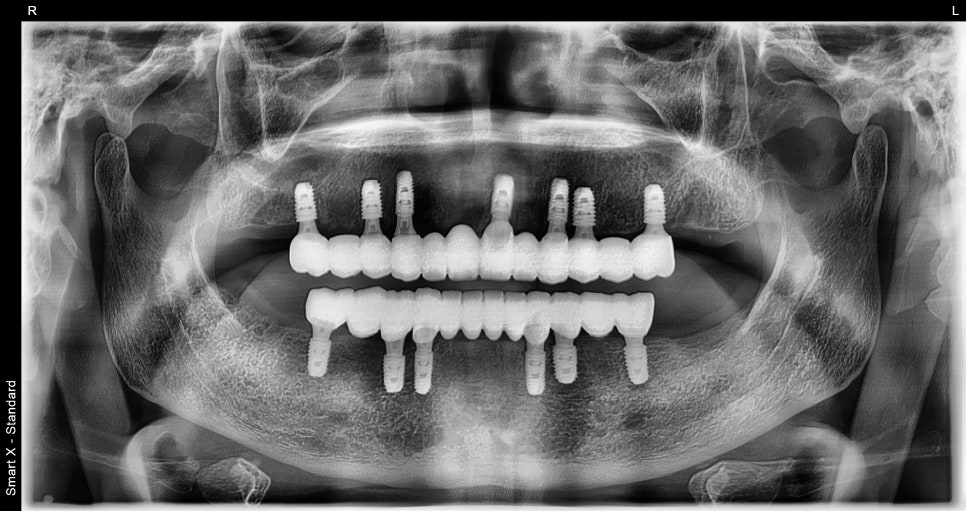

Seoulove Dental Hospital implants after

<After surgery>

- Placement of a total of 13 implants in the upper and lower jaws

- Bone grafting with allograft material where bone was insufficient

- Bite design centered on the molars

- Final prosthetics custom-made in our in-house lab

The full-mouth surgery included tooth extraction, bone grafting, sinus lifting,

and placement of all 13 full-mouth implants,

and it was completed in about 2 hours under sedation.

After placement, the front teeth and molars came together in a balanced way,

restoring a bite that allowed the patient to fully feel the texture of food.

- Normal eating became possible

- Chewing ability improved through restoration of the molar area

- Speech improved

- Facial expression and contour became more stable

- Gum inflammation decreased